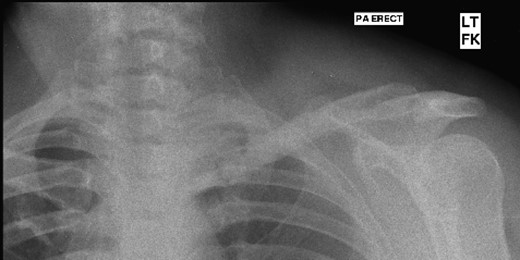

A 45-year-old woman presented with a 20-year history of a lump in the mid-third of the left clavicle, which had recently increased in size to 10 cm in diameter. Plain X-ray, computed tomography (CT) chest and clavicle, and bone scans were used to image the lesion (Figs 1–3). Radiology reported the lesion as a parosteal osteosarcoma, based on the CT appearance of tumour growing into the medulla of the mid-third of the clavicle; not usually a feature of an osteochondroma or an osteoma. Biopsies showed dense sclerotic bone, with no obvious malignant features. To confirm diagnosis complete excision of the tumour was needed, with a partial excision and scraping the lump off the surface deemed unsafe. The patient was informed that, following a total claviculectomy, a 30% functional loss (29.5% [8]) in her left shoulder power would be expected. Her active lifestyle meant this result was unacceptable, so she opted instead for excision of the tumour plus the adjacent clavicle, irradiation and reimplantation of the bone with internal fixation, despite this being relatively experimental. If successful, she would have virtually normal function. Although possible risks included infection or development of non-union, which would require further surgery or possible complete claviculectomy, it was deemed oncologically safe with a low risk of complications.